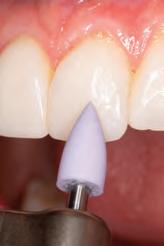

Surgical considerations

New parameters of restorative therapy require consideration of esthetic results that might require both periodontal and operative procedures to restore a harmonious integration and an esthetic balance of gingiva and tooth.34 Thus, periodontal plastic surgery procedures should be part of the clinician’s recipe for restoring the dentogingival complex. Traditionally, restorative therapy of teeth with gingival recession and carious or noncarious lesions has been achieved through operative procedures, with little attention given to the overall esthetic picture. In contrast, the perioesthetic approach considers the harmonious integration and interrelationship of the gingiva and tooth complex.35

In general, most clinical situations that present with gingival recession also involve a deficiency of keratinized attached gingiva, which requires mucogingival surgery.35 The periodontal plastic surgery procedures available for the treatment and correction of gingival recession include free gingival autografts, subepithelial connective tissue grafts, coronally positioned flaps, guided tissue regeneration, and acellular matrix grafts.36–41 These soft tissue grafts are indicated for the restoration of noncarious and carious cervical radicular lesions and for previously placed restorations associated with gingival recession. Recent advances in periodontal plastic surgery procedures have stimulated reassessment of the envelope technique and its modified version, the tunnel technique, for root coverage of single and multiple adjacent gingival recessions.36,42,43

The envelope technique originated in 1985 for single gingival recession defects.36,44 This procedure involved vertical incisions on either side of a tunnel preparation that

enabled placement of a subepithelial connective tissue graft within the tunnel to cover the gingival recession. The modified microsurgical technique eliminates the vertical incisions and allows the construction of a tunnel under the gingival tissue by means of a sulcular incision beyond the mucogingival line without raising a flap. This alteration of technique by using newly developed microsurgical instruments allows an undermining split-flap preparation of the facial tissues, ensuring improved blood supply, early wound healing, predictable root coverage, and esthetic postoperative results.45–53 This modified microsurgical approach simplifies the technique and allows for the treatment of multiple adjacent gingival recession defects in one surgical visit.

Clinical concepts demonstrated

The following clinical procedure illustrates the aforementioned clinical concepts using a methodologic approach for planning and restoring the maxillary anterior dentition.

A 31-year-old woman presented with cosmetic concerns regarding her smile and requested a conservative enhancement. After clinical and radiographic analysis, digital 35mm photographs were taken and reviewed by the restorative clinician, technician, and surgeon (Fig 1). A digital impression was taken of the maxillary and mandibular arches using an intraoral scanner (Trios 3, 3Shape; Fig 2), and a smile design was developed with NemoSmile Design 3D software (Nemotec; Fig 3a). This allows for a facially driven smile frame to be created using reference lines of facial and smile proportions and natural teeth shapes and textures from the digital library (Fig 3b).

After developing the simulated mock-up, a 3D-printed resin model was created using CAD software (Fig 4a), and a clear PVS matrix (Exaclear, GC America) was fabricated to replicate the printed diagnostic wax-up using a nonperforated tray (Fig

Fig 1 Preoperative clinical views of a 31-year-old woman presenting with diastemas and limited tooth visibility. (top) Portrait. (center row) Intraoral views. (bottom row) Smile.

4b). This matrix was used to create an intraoral motivational mock-up with bis-acryl composite (Luxatemp Ultra, DMG). This additive mock-up provides the interdisciplinary team with an intraoral translation for evaluation (Fig 5). Upon evaluation of the digital smile frame and the clinical translation, it was determined that multiple esthetic and restorative requirements were necessary for an optimal biologic framework, and the interdisciplinary team determined the best sequence for these procedures. The patient was presented with the interdisciplinary treatment possibilities that included restoring the maxillary anterior teeth and premolars with a minimally

invasive preparationless procedure or with less conservative veneer preparations. The restorative materials discussed included injectable resin composites and ceramic (ie, feldspathic, pressable, machinable). For an optimal biologic framework and health, it was determined that connective tissue grafting would be necessary for treatment of the recessiontype defects on the maxillary left central and lateral incisors, canine, and premolars. The patient opted for the conservative preparationless composite veneers using the injectable resin technique followed by a connective tissue surgical procedure using the tunneling technique.